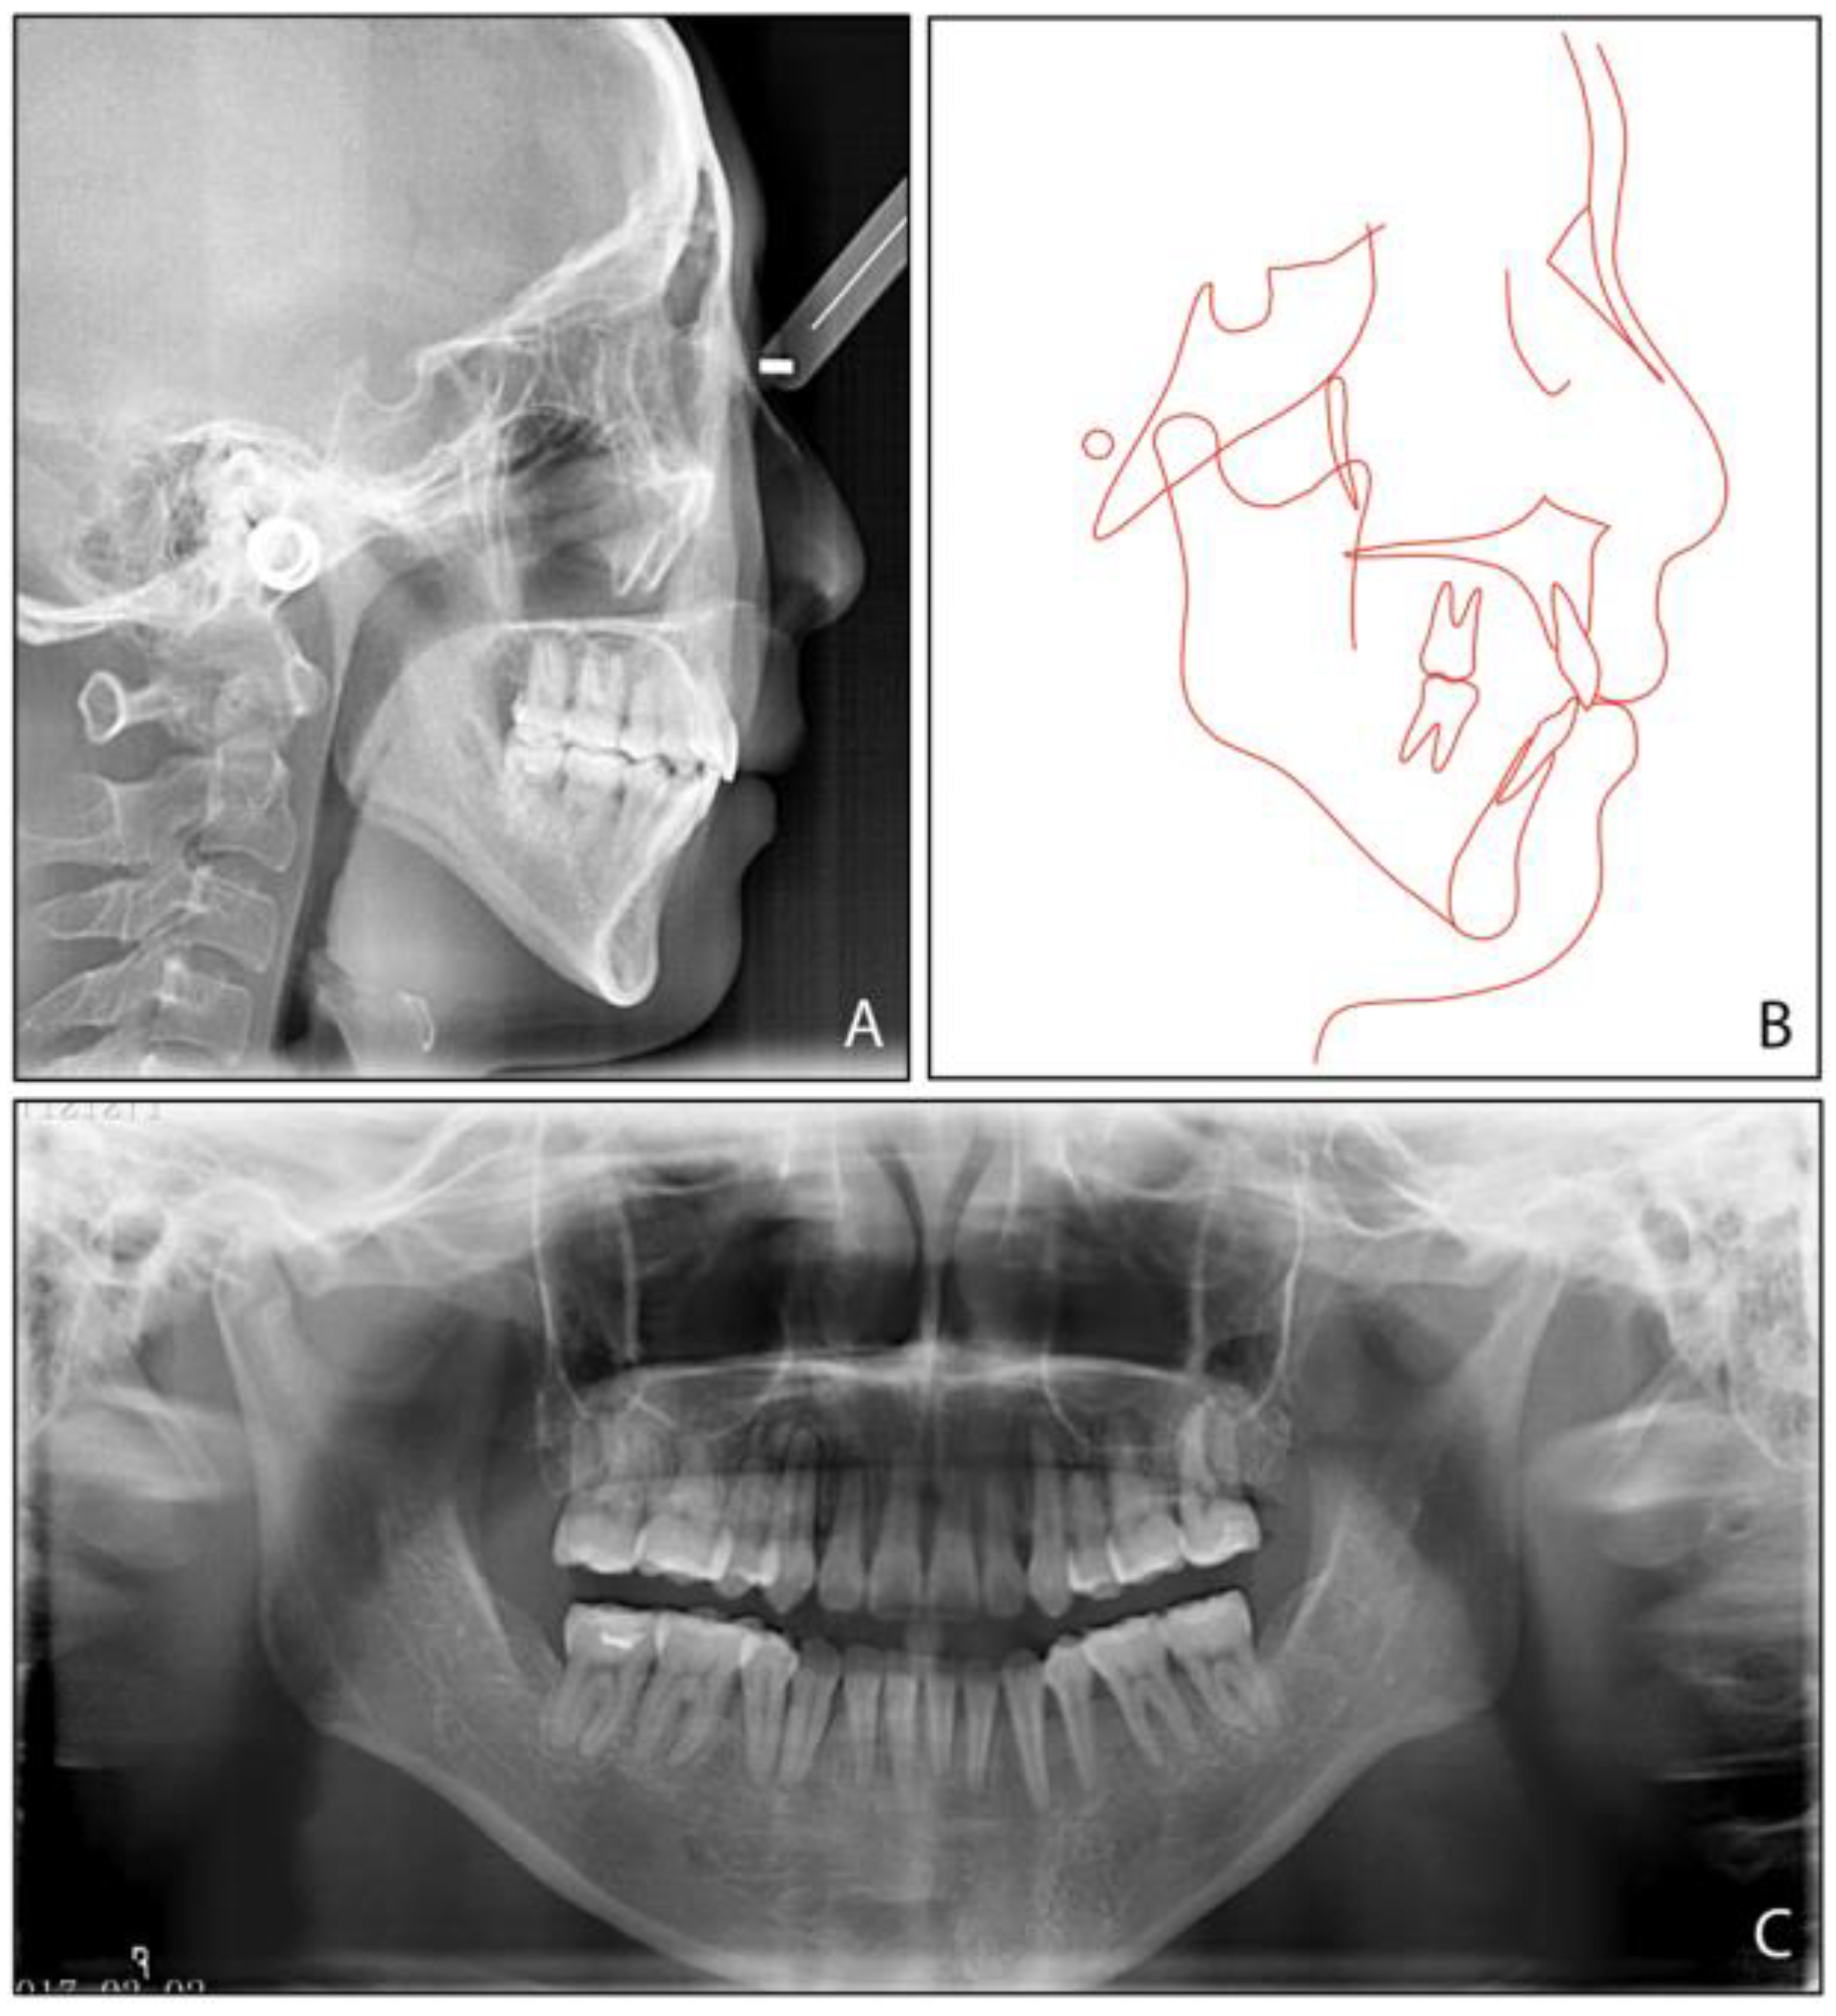

| Measurement | Normal Mean ± SD | Pretreatment | Posttreatment | Difference |

|---|---|---|---|---|

| SNA (°) | 83.1 ± 2.7 | 80.3 | 79.7 | −0.6 |

| SNB (°) | 80.3 ± 2.6 | 71.9 | 73.9 | 2 |

| ANB (°) | 2.7 ± 1.8 | 8.4 | 5.8 | −2.6 |

| UI-SN (°) | 103.4 ± 5.5 | 106.9 | 91.9 | −15 |

| LI-MP (°) | 96.3 ± 5.4 | 97.2 | 90.8 | −6.4 |

| UI-LI (°) | 129.1 ± 7.1 | 102.7 | 129.1 | 26.4 |

| MP-SN (°) | 32.6 ± 6.9 | 55.8 | 52.9 | −2.9 |

| MP-FH (°) | 25.5 ± 4.8 | 45.6 | 42.8 | −2.8 |

| Wits (mm) | −1 ± 1 | 5.8 | 2.8 | −3 |

| A-OP (°) | 10 ± 3.58 | 12.2 | 14.5 | 2.3 |

| P-OP (°) | 14.9 ± 3.85 | 25.1 | 16.2 | −8.9 |

| U1-PP (mm) | 28 ± 1.6 | 32.9 | 26.6 | −6.3 |

| U6-PP (mm) | 23 ± 1 | 24.4 | 19.3 | −5.1 |

| L1-MP (mm) | 40.8 ± 1.8 | 44.1 | 39.3 | −4.8 |

| L6-MP (mm) | 31.1 ± 1.9 | 33.4 | 28.9 | −4.5 |

| Palatal-OP (°) | 10 ± 4 | 17 | 15.7 | −1.3 |

| Upper Face Height (mm) | 50 ± 2.5 | 56.4 | 55.8 | −0.6 |

| Lower Face Height (mm) | 65 ± 4.5 | 81.1 | 75.4 | −5.7 |

| Anterior Face Height (mm) | 115 ± 5.5 | 135.9 | 130.8 | −5.1 |

| Posterior Face Height (mm) | 45 ± 5 | 75.9 | 73.2 | −2.7 |

| P-A Face Height (%) | 65 ± 4 | 55.8 | 56 | 0.2 |

| Y-Axis (°) | 67 ± 5.5 | 84.7° | 83.1 | −1.6 |

| UL-E (mm) | −1.6 ± 1.5 | 5 | −1 | −6 |

| LL-E (mm) | −0.2 ± 1.9 | 7 | −1.3 | −8.3 |